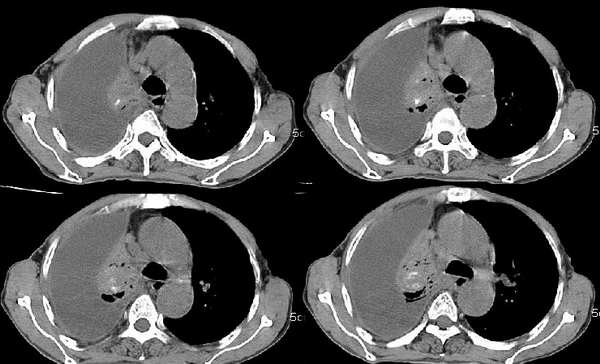

男,76岁,因心累,气紧加重,伴吐白色沫哝痰,偶尔有低烧,无盗汗。{门诊患者未见其它检查}

右肺上叶私有肿块,其内见条状 点状钙化,上叶后段支气管有阻塞征象,纵隔内见淋巴结影,大量胸水,陈旧性结核,肺癌不排除.

右肺毁损萎陷,其内可见钙化灶、残存空腔及支气管影。左上叶可见多发小结节影。纵隔左移,其内未见肿大淋巴结。右侧胸腔大量积液。考虑:肺结核并右肺毁损;右侧胸腔大量积液。

右肺萎陷,上叶似有肿块,其内见条状、点状钙化,上叶后段支气管有阻塞征象,纵隔内见肿大淋巴结影,右侧大量胸水,陈旧性结核。同时不排除在原有双肺结核的基础上出现右上肺癌并胸膜及纵隔淋巴转移的可能

支持右肺ca伴胸水,依据1有点状钙化肿块2支气管截断。最好抽胸水后再扫描,支气管镜检最好。

一看这个病人的定位片大致倾向恶性病变,因胸水漫顶,纵隔少偏.右上肺门旁肿块肯定,肺内肿瘤可能性很大.右上肺病灶多为陈旧性结核.实际上结核病并发肿瘤并非少见.所以二元论诊断也不奇怪.